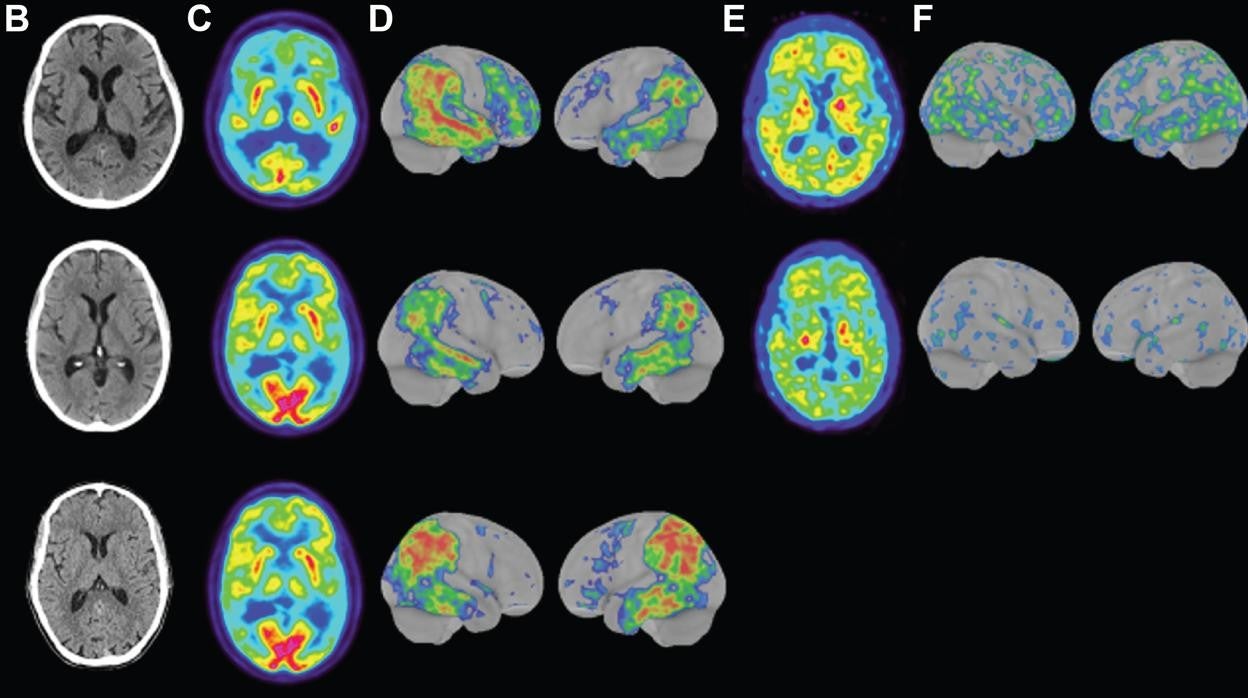

Los científicos también determinaron que tenían dificultades con las funciones ejecutivas, y los escáneres cerebrales revelaron las características del alzhéimer en los tres. Los escáneres cerebrales revelaron evidencia de atrofia en las regiones frontoparietal y mediotemporal del cerebro.